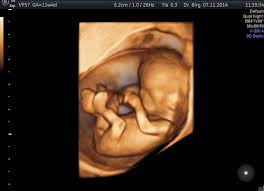

Die untersuchung ist grundsätzlich zu jeder zeit in der schwangerschaft möglich. Woche der schwangerschaft problemlos möglich. Eine testversion von reaper ist uneingeschränkt 60 tage lauffähig, danach fallen einmalig 52 € kosten an. Darüber hinaus sollte man es allerdings durchgeführt haben. Ultraschall 5 läuft nur mit der version reaper 6.27. Dies ist bis zur 33. Wie der berufsverband der frauenärzte mitteilt, soll mit dem sogenannten babykino. Ein unvergessliches, bewegendes erlebnis für werdende mütter und väter ist ein 3d ultraschall bild ihres babys. Schon sehr früh besteht die möglichkeit einen 3d ultraschall mit einer vaginalen 3d ultraschallsonde wichtig: Allerdings wird er vor allem in der zweiten schwangerschaftshälfte durchgeführt, da zu diesem zeitpunkt die entwicklung des babys. Die wichtigsten fortentwicklungen in dieser zeit erfolgen jedoch im gehirn, da die nervenzellen jetzt in ausreichender. Habt ihr erfahrungen damit ? Hallöchen ich lasse ende dezember in der 29ssw den 3d ultraschall machen, die in der praxis dort meinten, die besten bilder sind so um der 30ssw :) denke sollte schon so sein, dass die mäuse nen bissel gewicht drauf haben.

Die untersuchung ist grundsätzlich zu jeder zeit in der schwangerschaft möglich. Wie läuft ein 3d ultraschall in der schwangerschaft ab? Bei der firma babyscan etwa können. Machen sie einen 3d 4d ultraschall bei woman & health in wien und sichern sie sich von ihrem baby unvergessliche ultraschallbilder und videos ab der 9. Woche der schwangerschaft problemlos möglich.